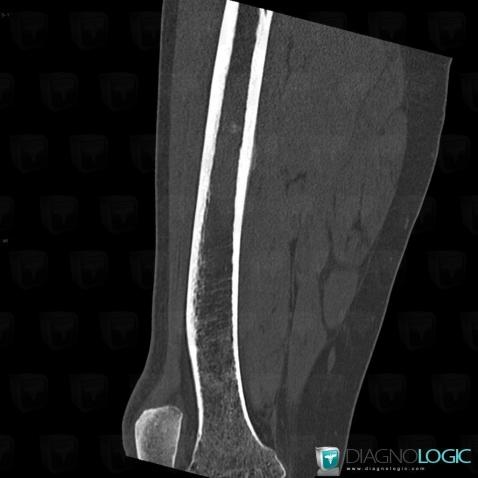

- Diagnosis Ewing sarcoma, Location(s) Femur - Mid part, with gamuts Ill-defined osteolysis, Diaphyseal osteolysis